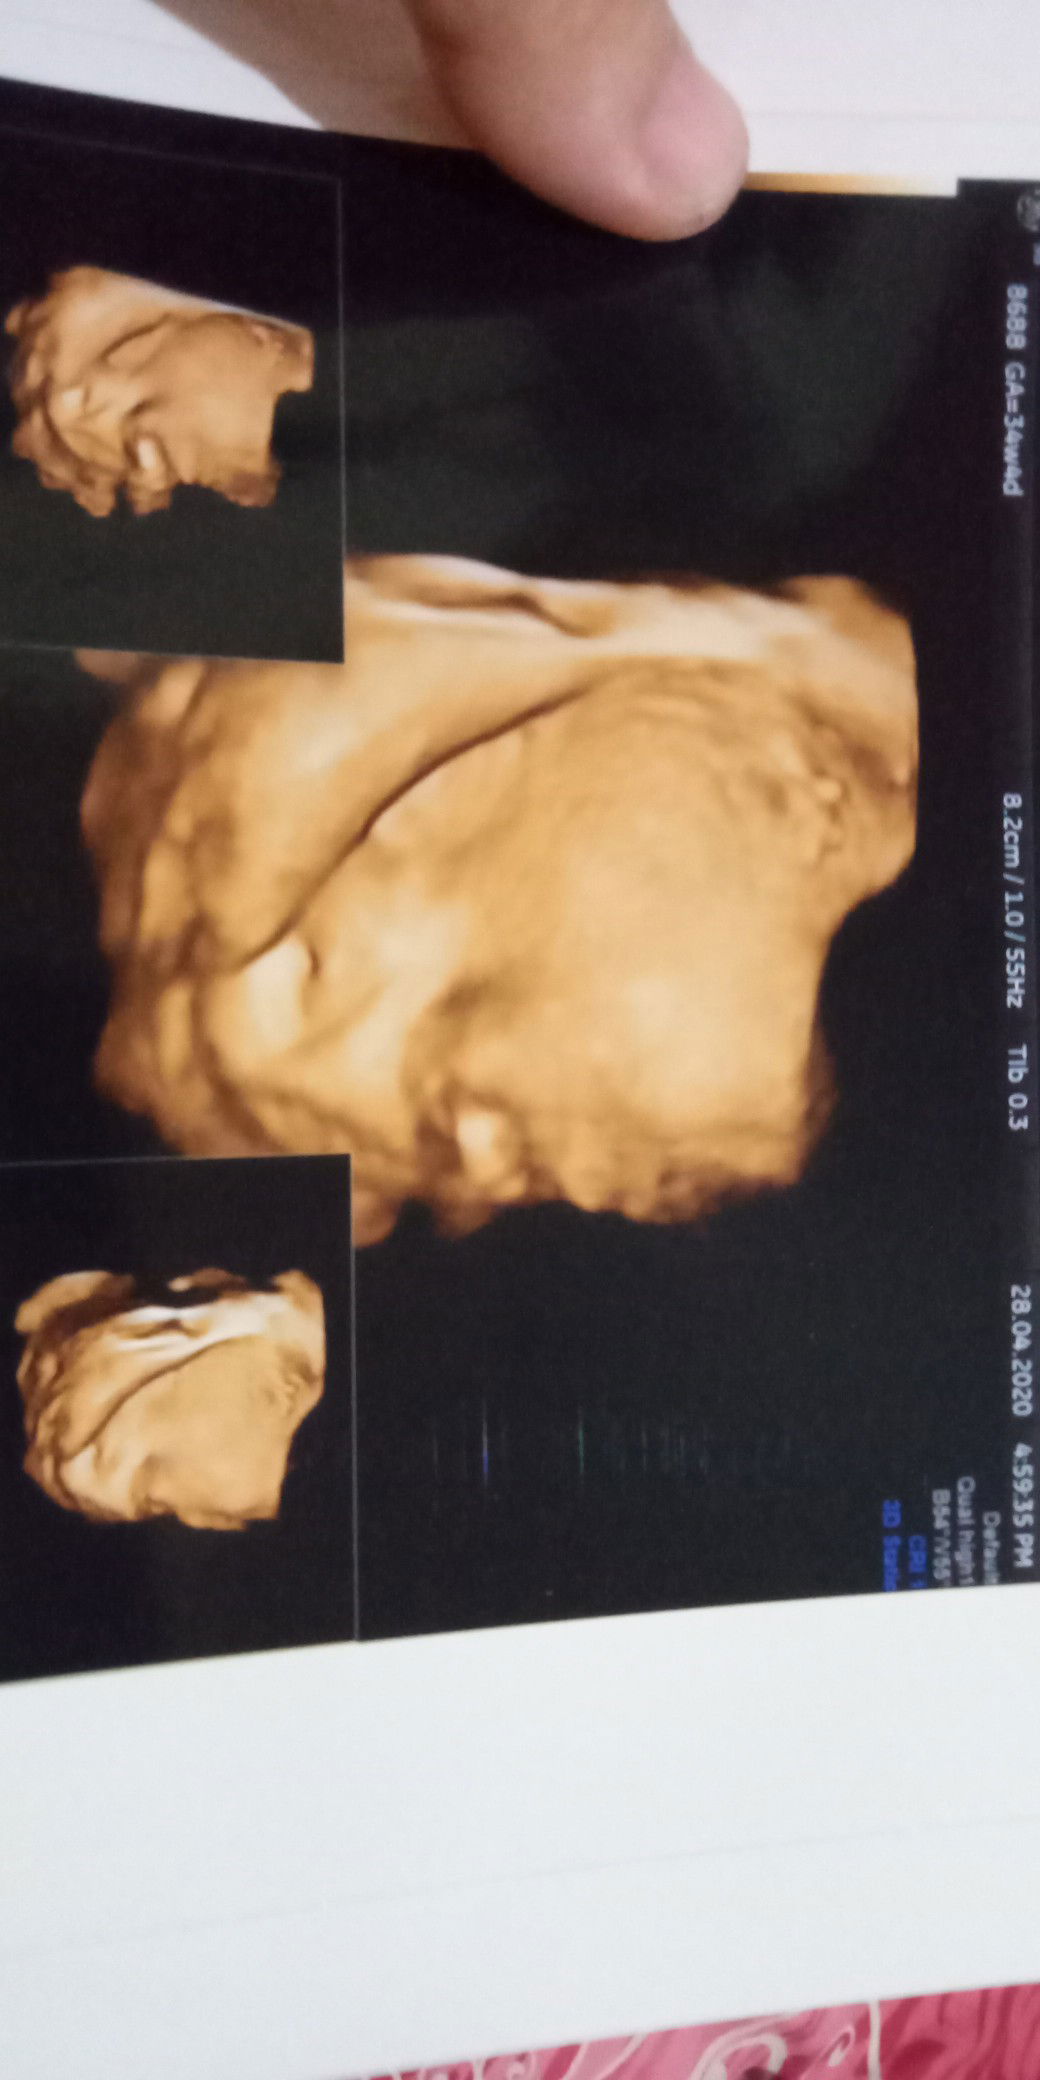

usg 4D

Bunda sore tadi saya habis USG ..kata dokter bbj saya kurang yg 1 nya 1,6 dan yg 1 nya lagi 2,1 ...saya dikasih waktu 2 Minggu lagi kata dokter harus naik bbj saya ...disuruh minum air putih bnyak2 n minum es cream Selain itu apa lagi ya Bun ...mohon infonya dong Bun yg pernah ngalamin kayak saya Hamil ukuran 34 week 4 D